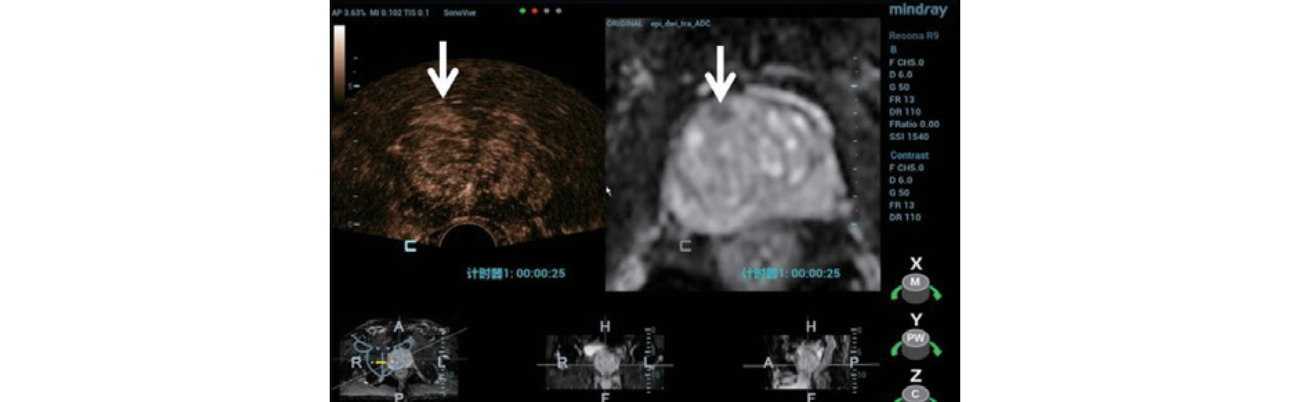

Step 2:?Using MindrayŌĆÖs iFusion software, the TRUS and MRI images were aligned and fused (Figure 3) and the target was labeled (Figure 4).

Step 3:?To verify the lesion location, a contrast enhanced ultrasound (CEUS) was performed using the MRI image for anatomical reference (Figure 5).

Step 4:?Under TRUS/MRI fusion guidance, a 12 core systemic biopsy was performed, followed by a targeted biopsy including 3 samples from the suspected lesion. (Figure 6) No complications were seen post procedure.

Pathology result: All 12 systemic punctures demonstrated benign prostatic hyperplasia. One of the three targeted punctures revealed prostatic adenocarcinoma.

Systemic biopsy is the current main diagnostic method for PCa. As the biopsy sites are standardized rather than targeted at a particular suspicious lesion, this method may also result in missed diagnosis or underestimation of disease. Multi parameter MRI has a high sensitivity and specificity for the diagnosis of PCa, however, MRI guided biopsy is complicated and expensive. Mindray iFusion software on the Resona 9 provides a solution by fusing the MRI dataset with live ultrasound imaging. Using bi-plane TRUS/MRI fusion guidance for targeted prostate biopsy improves the accuracy of clinical prostate cancer diagnosis [2].

In this case, the suspicious lesion was detected on MRI and using iFusion navigation the corresponding plane and target area were labeled on ultrasound. A CEUS exam provided additional diagnostic information and three guided biopsies were performed into the suspect area. While the standard 12-point samples were negative, one of the targeted samples came back positive for PCa. This case clearly shows how biplane TRUS/MRI fusion targeted biopsy can help avoid missed diagnosis and improve diagnostic accuracy.